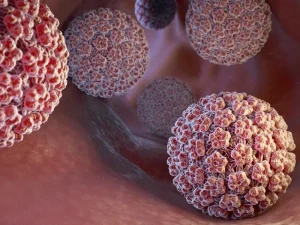

کولپوسکوپی زگیل تناسلی یک روش تشخیصی دقیق و کمتهاجمی است که با بزرگنمایی بافتهای دهانه رحم، واژن و ناحیه تناسلی، امکان شناسایی تغییرات ناشی از

آیا زگیل تناسلی در بارداری برای خطرناک است و مشکلی برای جنین ایجاد می کند؟ بارداری دورهای حساس در زندگی هر زن است که تغییرات

آیا ویروس HPV واقعا خطرناک است؟ پاسخ اینجاست

ویروس HPV یکی از شایعترین عفونتهای ویروسی در جهان است که در اکثر موارد از طریق تماس جنسی منتقل میشود و سلامت دستگاه تناسلی را